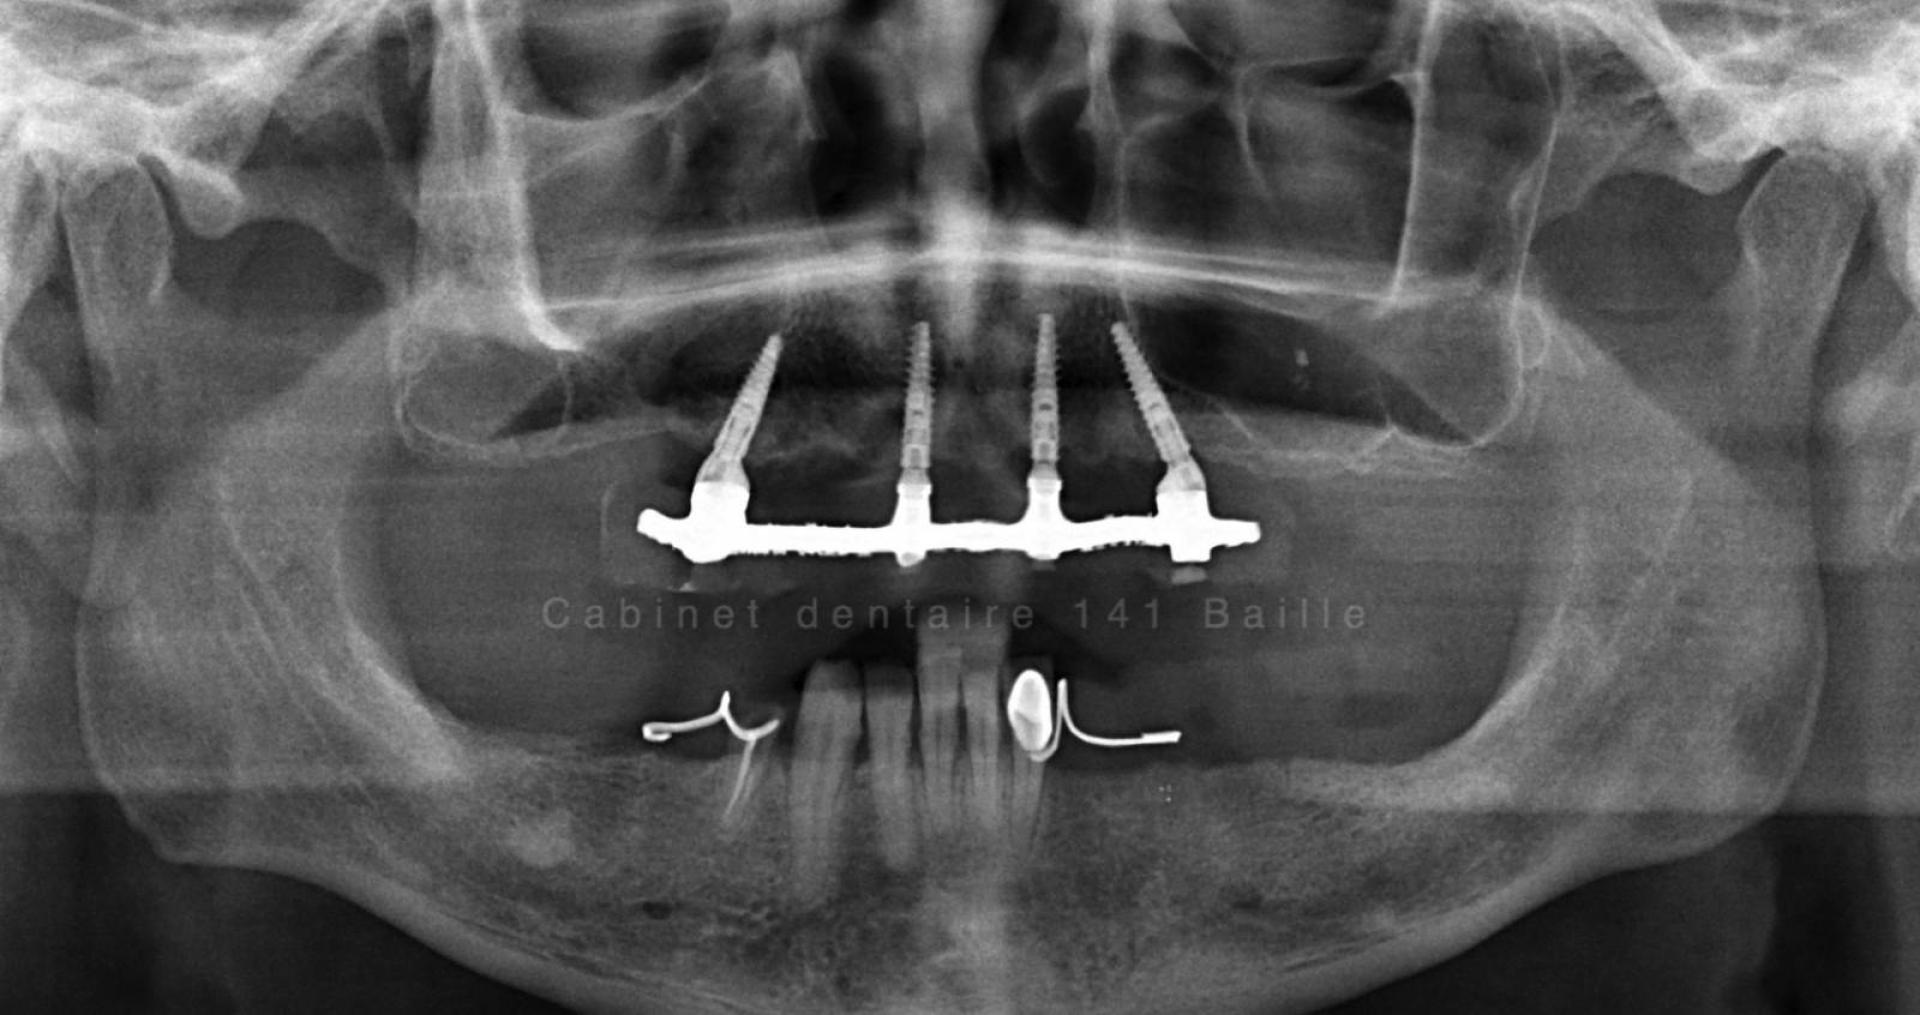

L'implant dentaire est une sorte de cheville que le chirurgien dentiste implantologue place dans l'os alvéolaire.

La tenue de l'implant est conditionnée par des facteurs de biomécanique ,qui dépendent essentiellement de la qualité de l'os et de sa quantité sur le site receveur de l'implant.En cas de manque de volume osseux ,il sera impossible sans réaliser de greffe osseuse dentaire préalablement à la pose de l'implant d'envisager ce type de technique.

On parle alors de Régénération Osseuse Guidée (ROG).Ces techniques de chirurgie avancée pré-implantaire ont énormément évolué et permettent aujourd'hui d'étendre les possibilité du traitement par implant dentaire aux patients ayant eu une forte perte d'os.

Le principe est de créer  un volume d'os plus important par des techniques de coffrage et d'isolation par des membranes spécifiques qui permettent à l'os alvéolaire de se différencier sans être envahi par les cellules de la gencive.

On est dans des techniques de chirurgie osseuse avancées qui nécessitent un environnement stérile et des compétences particulière de la part du chirurgien implantologue.